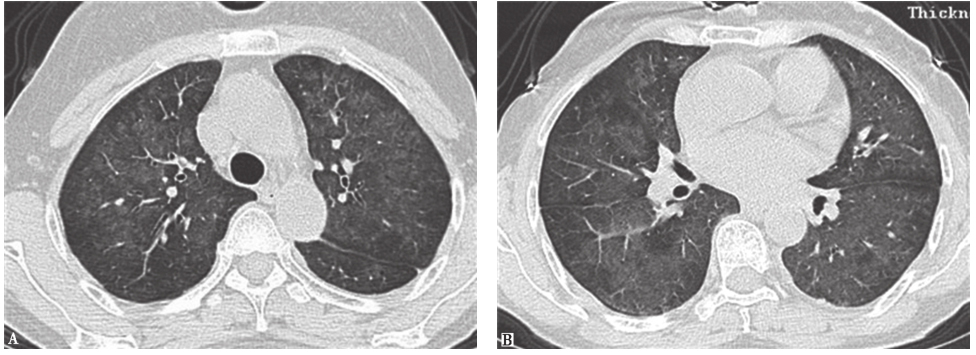

【影像学检查】

外院胸部CT示两肺散在磨玻璃影、弥漫性小结节影(图1),局部可见牵拉性支气管扩张。

两肺散在磨玻璃影及小结节影(图13),局部网状影,较入院前(图1)明显吸收、好转。